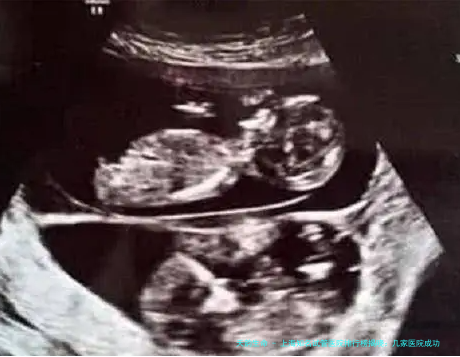

上海试管流程一般来说蕴藏咨询、体检、促排卵、采卵、胚胎培育、移植和验孕等方法。每一个步调都须要病患协同医生的安排和引导,以保证全过程的顺当进行。